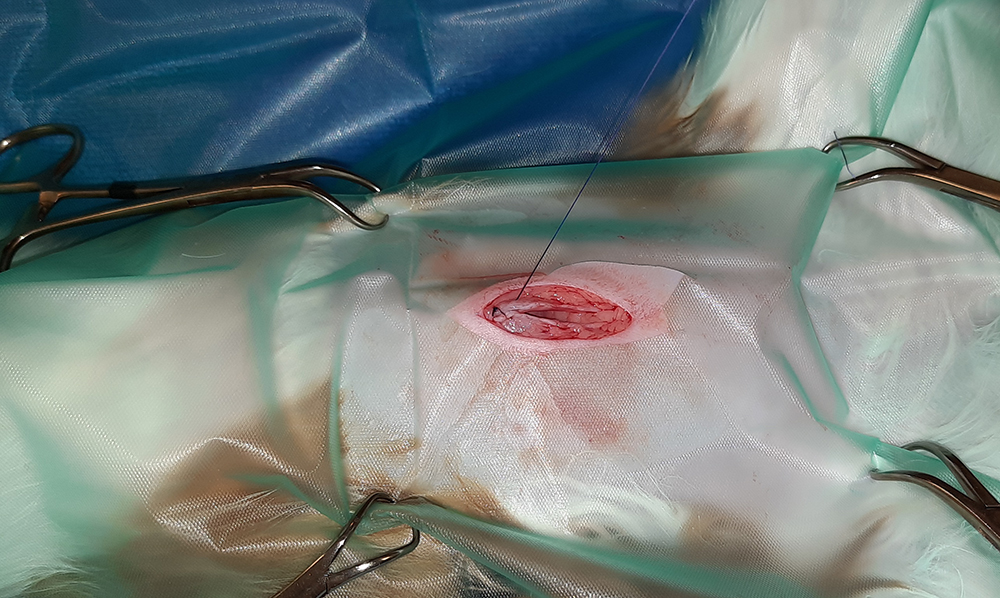

Er wordt een kleine snede gemaakt in de buik, ter hoogte van de navel. Vervolgens worden na elkaar de twee ovaria (=eierstokken) opgezocht, de aanvoerende bloedvaten afgebonden en de eierstokken verwijderd. Hierna wordt de buik in 3 lagen gesloten; de spierlaag, de onderhuid en de huid. Deze laatste wordt onderhuids gesloten met soms een enkele uitwendige knoophechting, zodat er zo min mogelijk hechtingen zichtbaar zijn. Er wordt een wondpleister geplaatst, nadat het wondgebied voorzichtig is schoongemaakt.